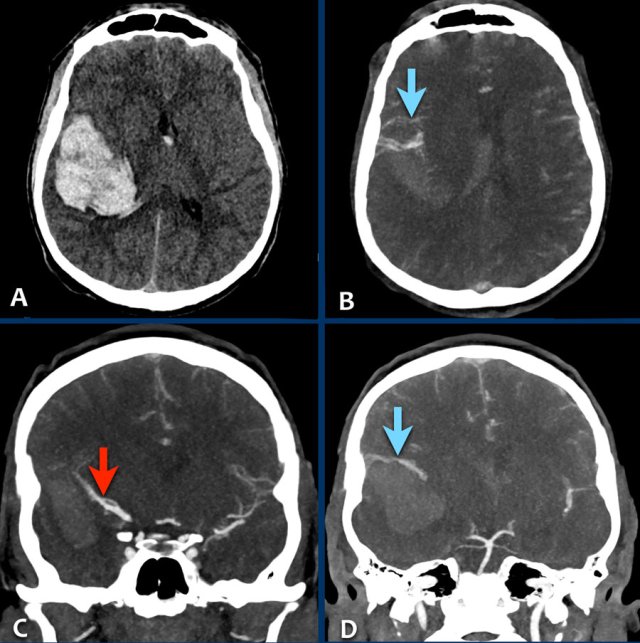

dAVF 1

This patient suffered from an intraventricular hemorrhage.

Note the cortical venous reflux (arrowheads) on the CT-angiography with also venous ectasia (yellow arrow) near the temporal horn of the lateral ventricle as the bleeding spot.

The DSA images (lateral view) confirmed a dural arteriovenous fistula (DAVF) Borden type 3, Cognard type IV.

Note the massive cortical venous reflux with venous ectasia.

Embolization with liquid agent (arrow) Embolization with liquid agent (arrow)

After trans-arterial embolization with liquid embolic agents (arrow), there was a complete obliteration of the DAVF.